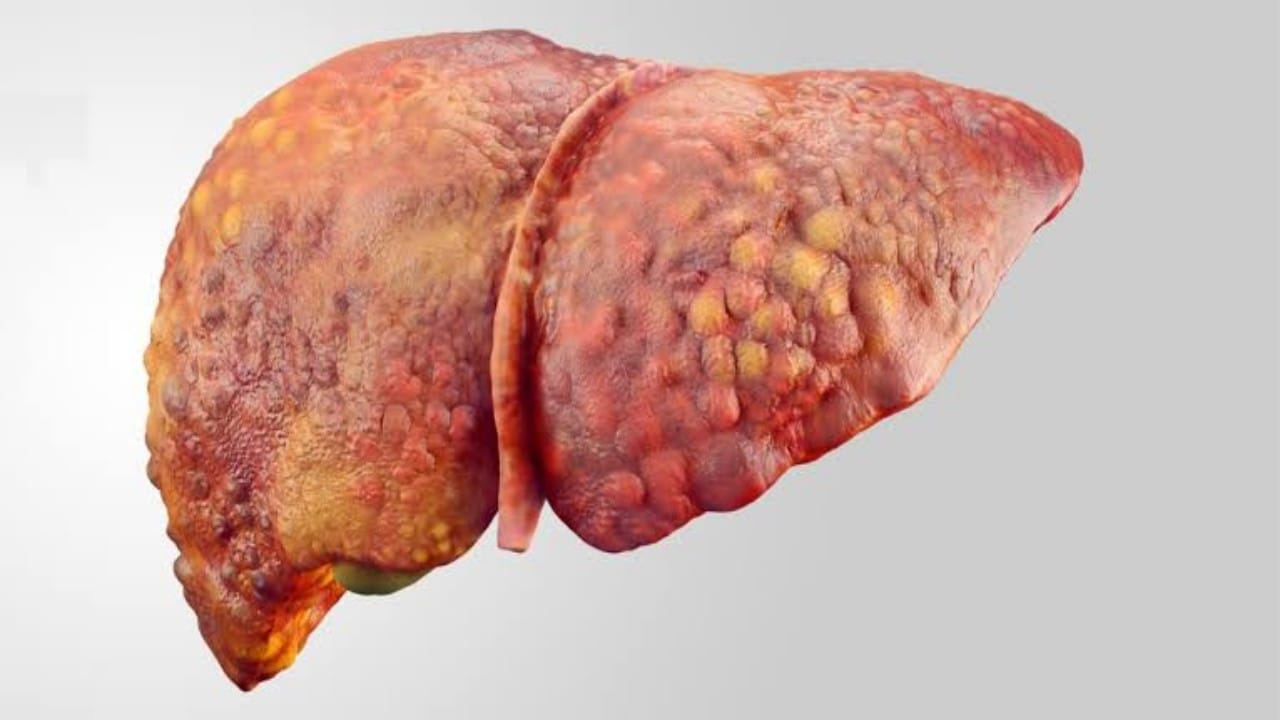

استشاري يكشف عن طريقة بسيطة لإرجاع نسيج الكبد إلى حالته الطبيعية